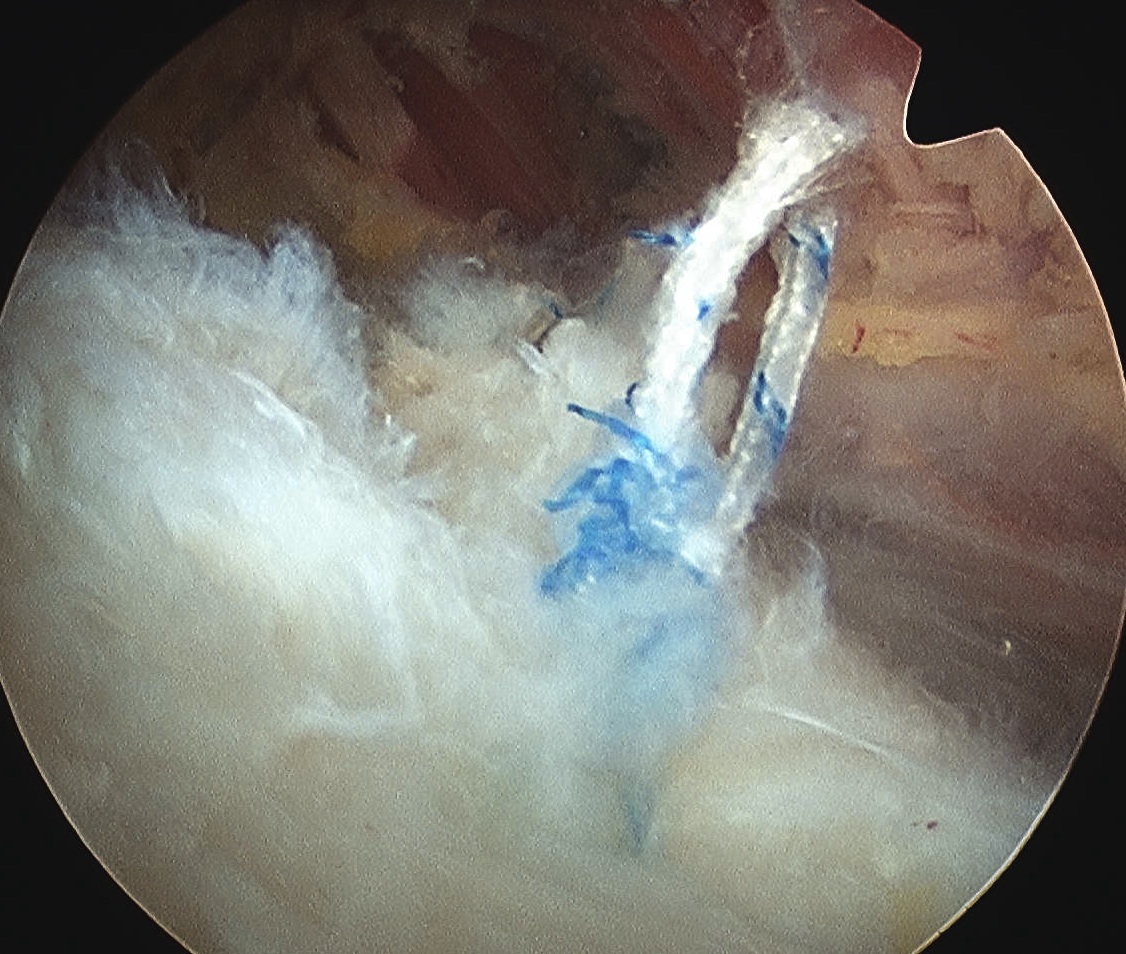

D. Transosseous equivalent / suture bridge

Technique

- biomechanically replicate tradional open transosseous

- sutures crossed as below in double row

- aiming to increase contact between cuff and footprint

Double row

- either pass second lateral row of anchors or

- use foot print anchors, retrieve previous sutures

- can make suture bridge configuration

- check repair via lateral portal